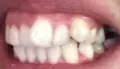

Мне 24 года. С 13-15 лет носила брекеты. В 19 прорезались зубы мудрости, и зубы верхней челюсти стали выступать из зубного ряда. Мучиться с брекетами больше не хочу.

Подскажите, есть ли ещё варианты исправления такой ситуации как у меня, хотя бы эстетически? Может виниры или элайнеры какие?

Конечно нельзя, проблема, действительно, связана с восьмыми зубами, которые необходимо удалить как можно раньше и после обратиться к ортодонту. К сожалению, выпирающий зуб настолько вылез из зубного ряда, что даже обточка и установка коронки в Вашем случае не дадут хороших результатов, да это и неправильно.

Так что выход один, хотите Вы или нет — брекеты!